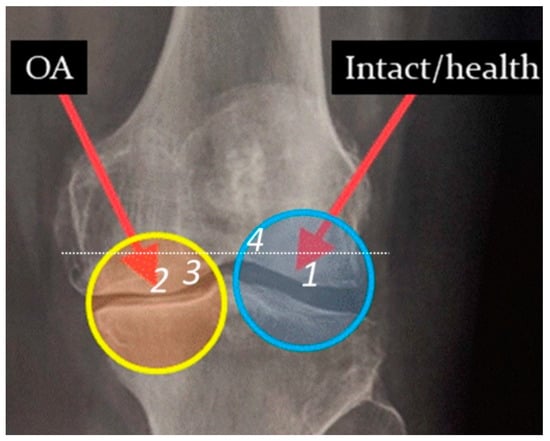

The medial and lateral condyles of the femur resected during total knee arthroplasty in patients with medial compartmental knee OA were used as samples to study changes in the local electronic and atomic structure of the subchondral bone. Figure 1 displays a radiograph of the OA-damaged knee joint. The sample of healthy bone is a saw-cut of the condyle of femoral bone, not subjected to excessive loads, with intact cartilage (area 1 in Figure 1). The bone sample of the damaged area is a saw cut of the same femoral bone, subjected to excessive mechanical stress due to the development of OA and deformity in the joint, with full-layer loss of cartilage. The area referring to the sclerotic bone is labeled as 2 in Figure 1. Just outside 2 there is a contact region with erased cartilage marked as 3. Such a choice of objects makes it possible to analyze the subsequence of spatial changes in the bone under the action of mechanical loads.

Figure 1.

OA-damaged knee joint: different areas on proximal side of the femur: intact 1, sclerotic bone 2, and its vicinities 3. Dots show the position of the distal side (area 4) of saw-cuts under study.